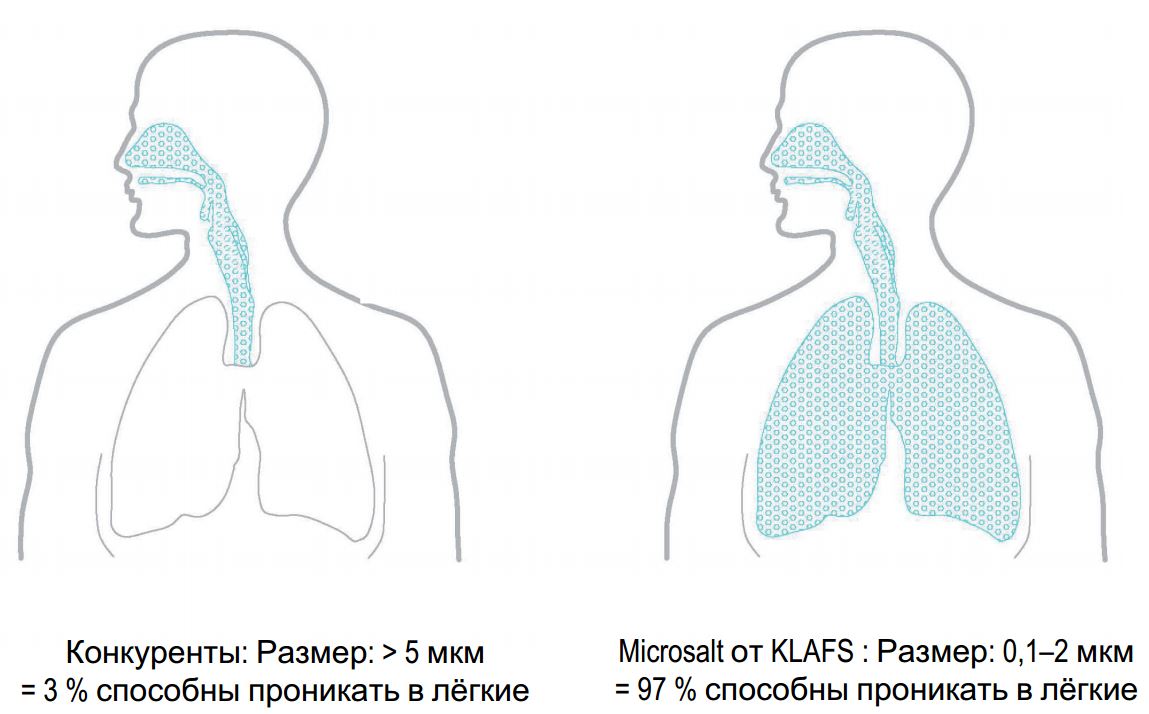

- Оптимальный размер частиц 0.1-2 мкм, определенный с помощью запатентованного метода. Способность проникать в легкие от околоносовых придаточных пазух до альвеол

- Размер частиц: 97% <2 мкм (способны проникать в легкие)

Сравнение Microsalt от KLAFS с другими производителями: